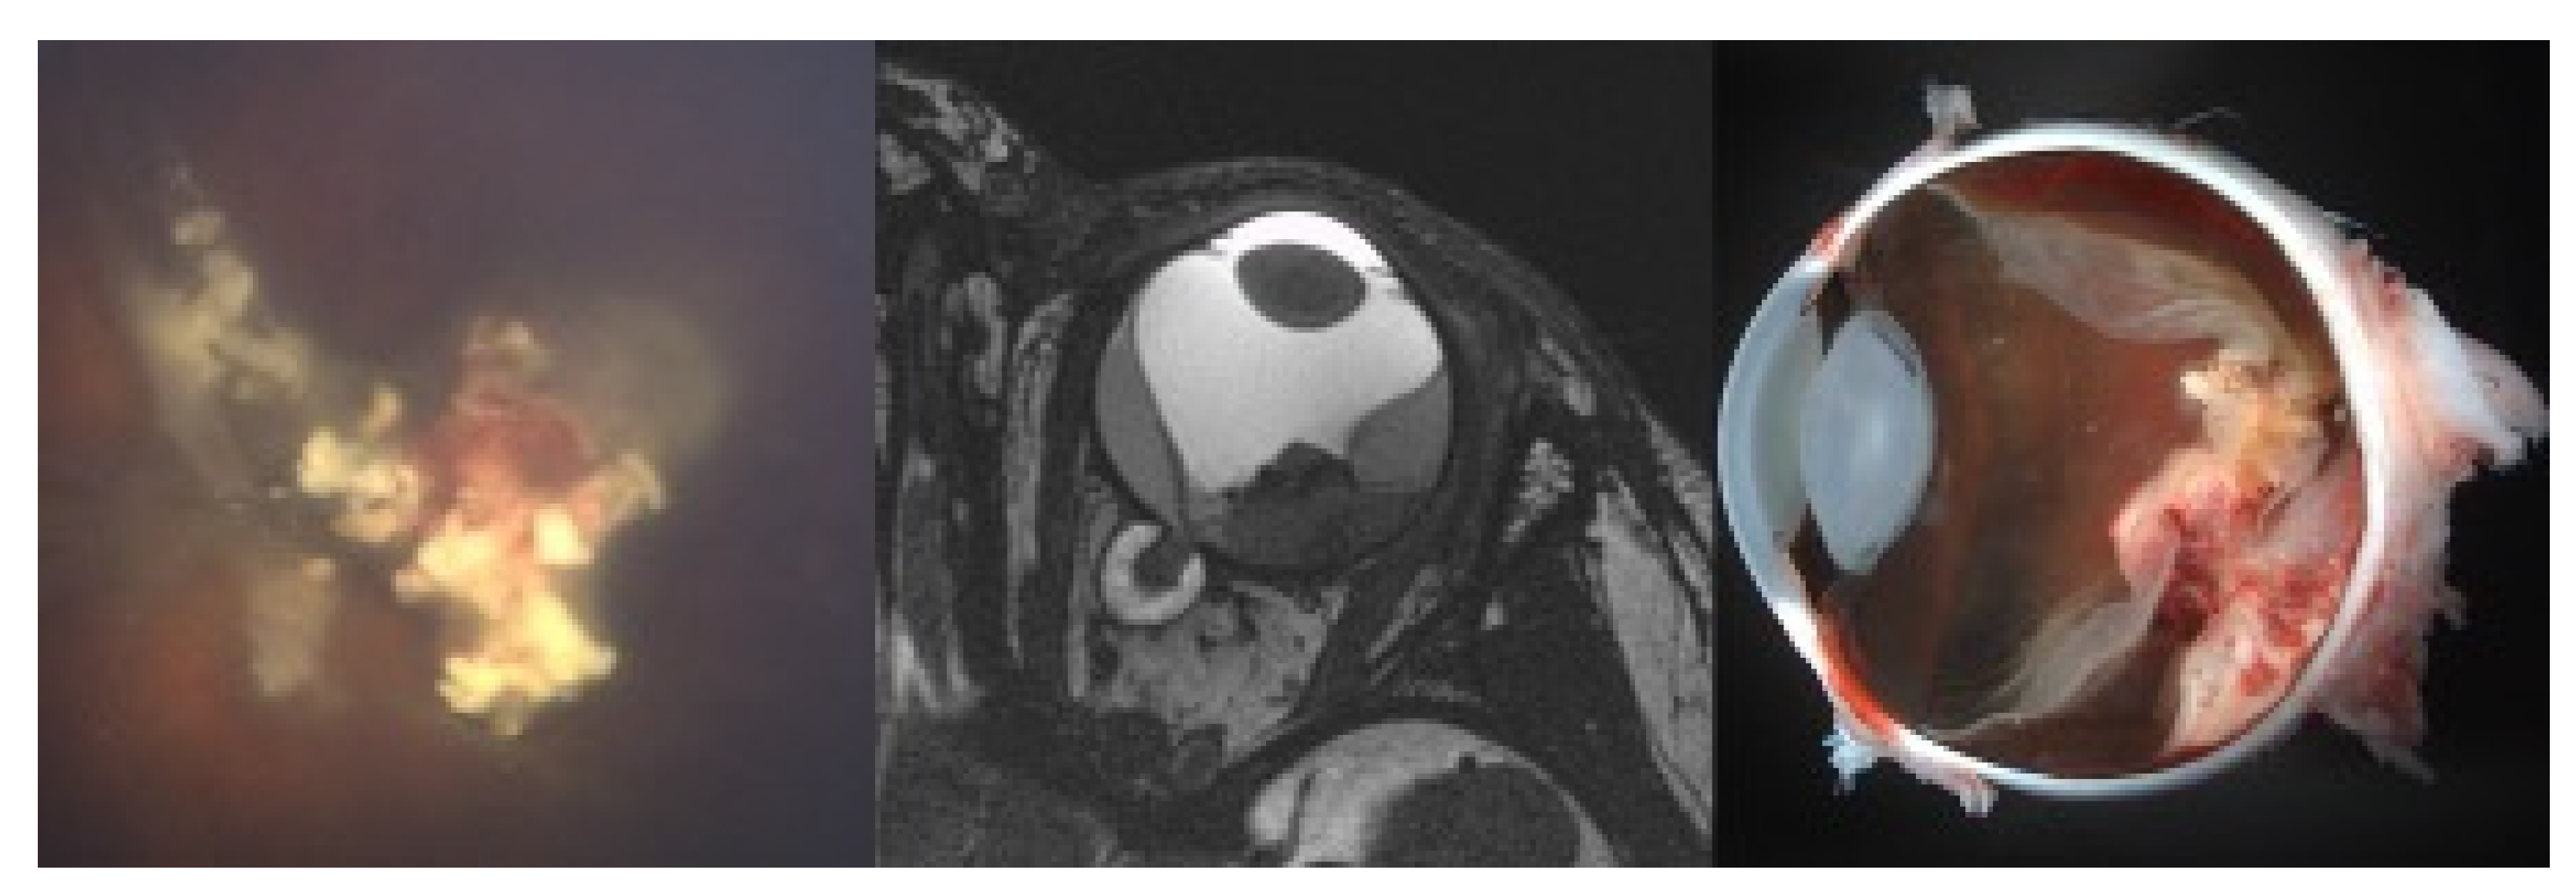

PBT was performed as described above. Figure 1 displays the irradiation plan of a tumor recurrence at the posterior pole with the corresponding MRI scan and RETCAM™ images before and after irradiation.

Figure 1. (Case 2): 21 old month male patient before and after proton beam therapy. The top figure shows the irradiation plan (gross tumor volume (GTV): red and clinical target volume (CTV): yellow) and middle figure the corresponding magnetic resonance imaging (MRI) before proton beam therapy (PBT). Note the sparing of the lens and the small bony window. The lower left picture shows two recurrent tumors close to the optic disc. Intraarterial chemotherapy was not feasible due to insufficient visualization of the ophthalmic artery. The lower right picture shows the result after a follow-up of 16 months. Best-corrected visual acuity was 20/40 Snellen acuity.